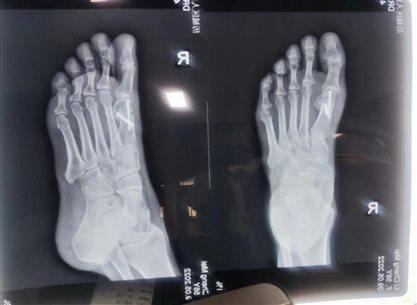

拇外翻手术,去除骨赘,不但清除干净,不留骨沫,而且能把歪趾矫正,通过术前术后X光片即可看出,所以,微创拇外翻矫正术后不会复发,远期效果非常好。

以下是我院外一科拇外翻患者手术前后对比:

术后复查X线